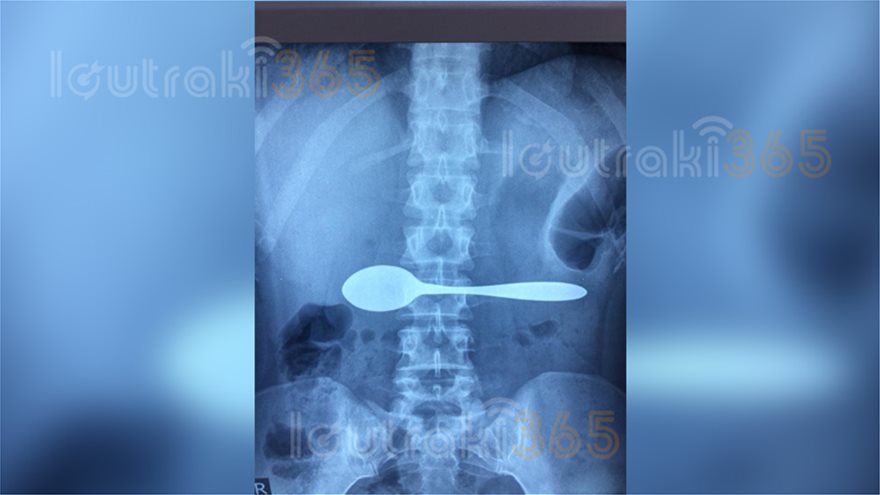

Η 35χρονη, τους εξήγησε ότι καταλάθος, κατάπιε ένα κουτάλι. Οι γιατροί του Νοσοκομείου, της είπαν να βγάλει αμέσως ακτινογραφία για να διαπιστώσουν αν όσα έλεγε η Κορίνθια ασθενής, ανταποκρίνονταν στην πραγματικότητα.

Και όμως. Μόλις η ακτινογραφία επιβεβαίωσε τα όσα έλεγε η 35άχρονη, οι γιατροί του Νοσοκομείου Κορίνθου την έστειλαν αμέσως σε εφημερεύον Νοσοκομείο της Αθήνας, καθώς έπρεπε να εξετασθεί από γαστρεντερολόγο που δεν υπήρχε στο Νοσοκομείο Κορίνθου.

Η ακτινογραφία της 35χρονης από το Ξυλόκαστρο: